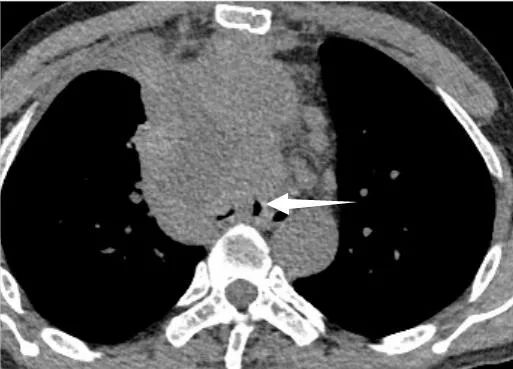

支架置入前(图 1 为 CT 冠状位,红色箭头提示肿物阻塞气道;图 2 为 CT 纵隔窗,白色箭头所指为气道肿物;图 3 为气管镜下图像,红色箭头所指为气道肿物。)

为充分保障患者安全,治疗团队决定对患者先用 ECMO 来改善氧合,之后再进行手术。重症医学科团队有条不紊地为患者进行双侧股静脉置管,连接人工肺管路,使患者血氧饱和度维持在 95% 以上。而在患者的另一边,呼吸介入团队快速插入硬质支气管镜,镜下可见患者气管下段气管已被完全堵塞。